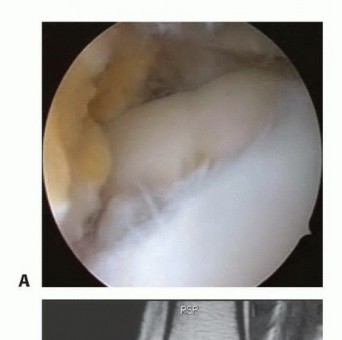

DEFINITION Patellofemoral pain is a common symptom in active adolescents and adults. The diagnosis of patello…